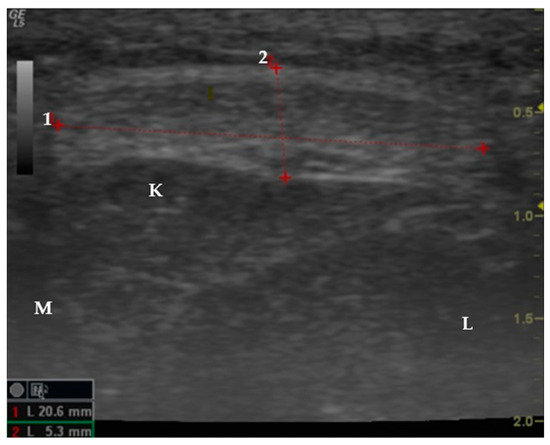

2.2. Study Design

2.3. Data Collection